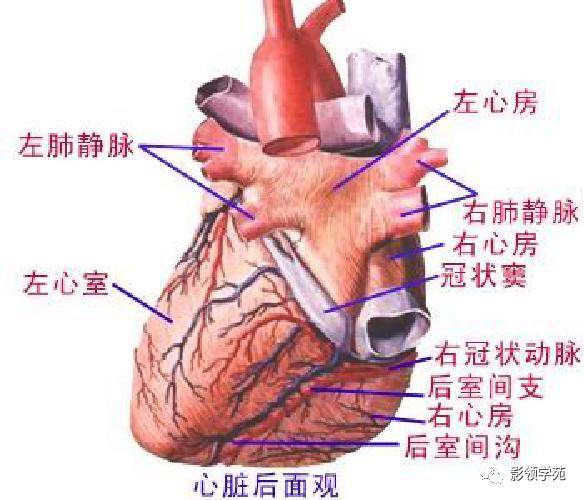

心血管系统

心血管系统